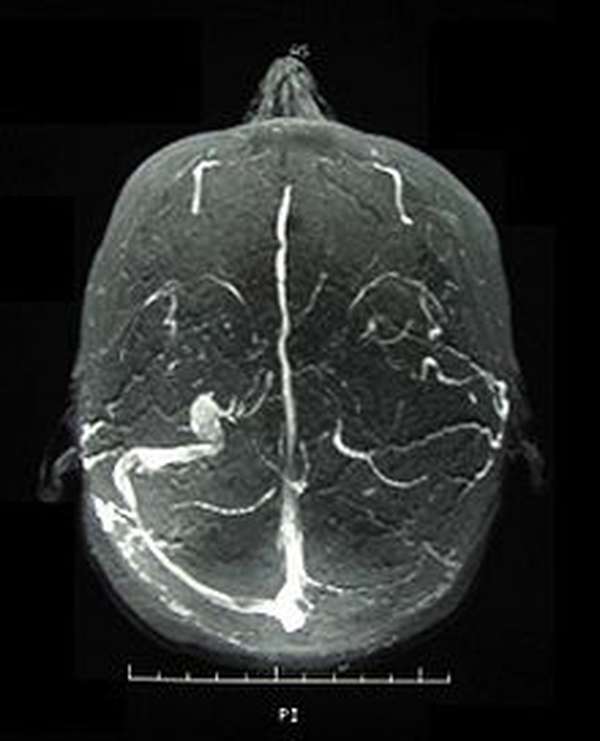

Xét nghiệm máu toàn bộ (CBC), xét nghiệm bảng chuyển hóa toàn diện (CMP), chụp cắt lớp vi tính (CT Scan), xét nghiệm nước tiểu.

Click vào ảnh để xem 3 hình ảnh minh họa